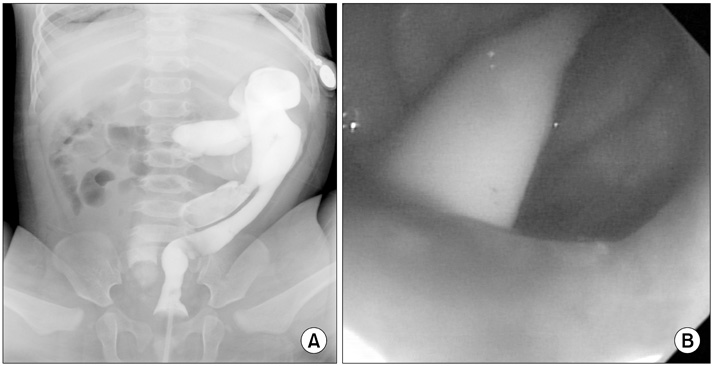

A 2-month-old female infant presented to our hospital with a 1-month history of stool passing through the vagina. She was born at 36 weeks' gestation weighing 1.875 kg and was the second infant of a twin. She had a ventricular septal defect that closed spontaneously at 1 month of age. Initially, she was diagnosed with a rectovaginal fistula. Despite conservative therapy, including a sitz bath, for 5 months, there was no improvement in her symptoms, and most of the stool still appeared to pass through the vagina. A colon study indicated a rectovaginal fistula directly connected to the distal rectum (

Fig. 1). Under general anesthesia, a small opening located posterior to and near the vagina at vestibule was found. The structure that had been misdiagnosed as a fistula based on the colon study was not present. The patient had a normally sited anus, an anterior ectopic anus, and a double vagina (

Fig. 1A preoperative colon study appeared to show that the contrast had passed to the vagina through a rectovaginal fistula (arrows).

Fig. 2Examination under general anesthesia revealed a normal anus, an anterior anorectal duplication (catheter-inserted state), and duplicate vaginal openings.